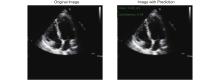

Holste G, Oikonomou EK, Mortazavi BJ, Coppi A, Faridi KF, Miller EJ, et al. Severe aortic stenosis detection by deep learning applied to echocardiography. Eur Heart J 2023; 44: 4592-4604.

Huang Z, Long G, Wessler BS, Hughes MC. Tmed 2: a dataset for semi-supervised classification of echocardiograms. In DataPerf: Benchmarking Data for Data-Centric AI Workshop 2022.

Huang Z, Long G, Wessler B, Hughes MC. A new semi-supervised learning benchmark for classifying view and diagnosing aortic stenosis from echocardiograms. Machine Learning for Healthcare Conference 2021; 149: 614-647.